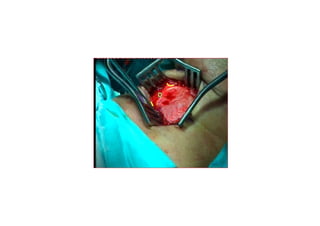

MedializasyonMedializasyon (Tip I)(Tip I) tiroplastitiroplasti

TTiroidiroid kk kk rdakta ardakta açç lanlan penceredenpencereden

yerleyerle((tirilen birtirilen bir implantimplant aracarac ll ileile

VFVF’’ unun medialmedialee itilmesiitilmesi

5 mm

PreopPreop

PostopPostop

1. hafta1. hafta

3. ay3. ay

MedializasyonMedializasyon (Tip I)(TipI) tiroplastitiroplasti TTiroidiroid kk kk rdakta ardakta açç lanlan penceredenpencereden yerleyerle((tirilen birtirilen bir implantimplant aracarac ll ileile VFVF’’ unun medialmedialee itilmesiitilmesi